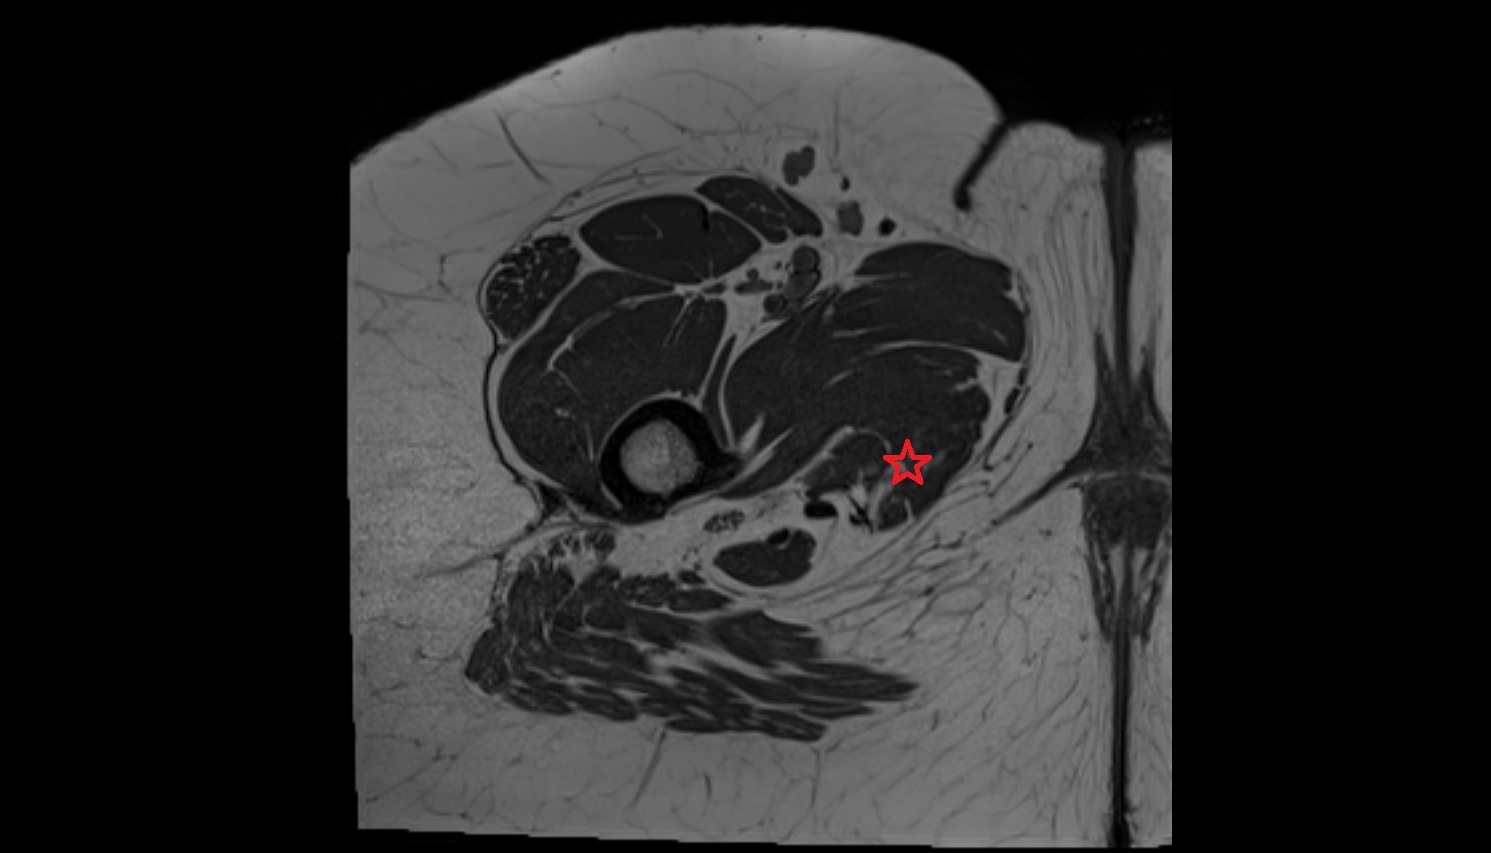

- Sciatic nerve

- Deep femoral artery (profunda femoris)

- Femoral artery

- Superficial femoral artery